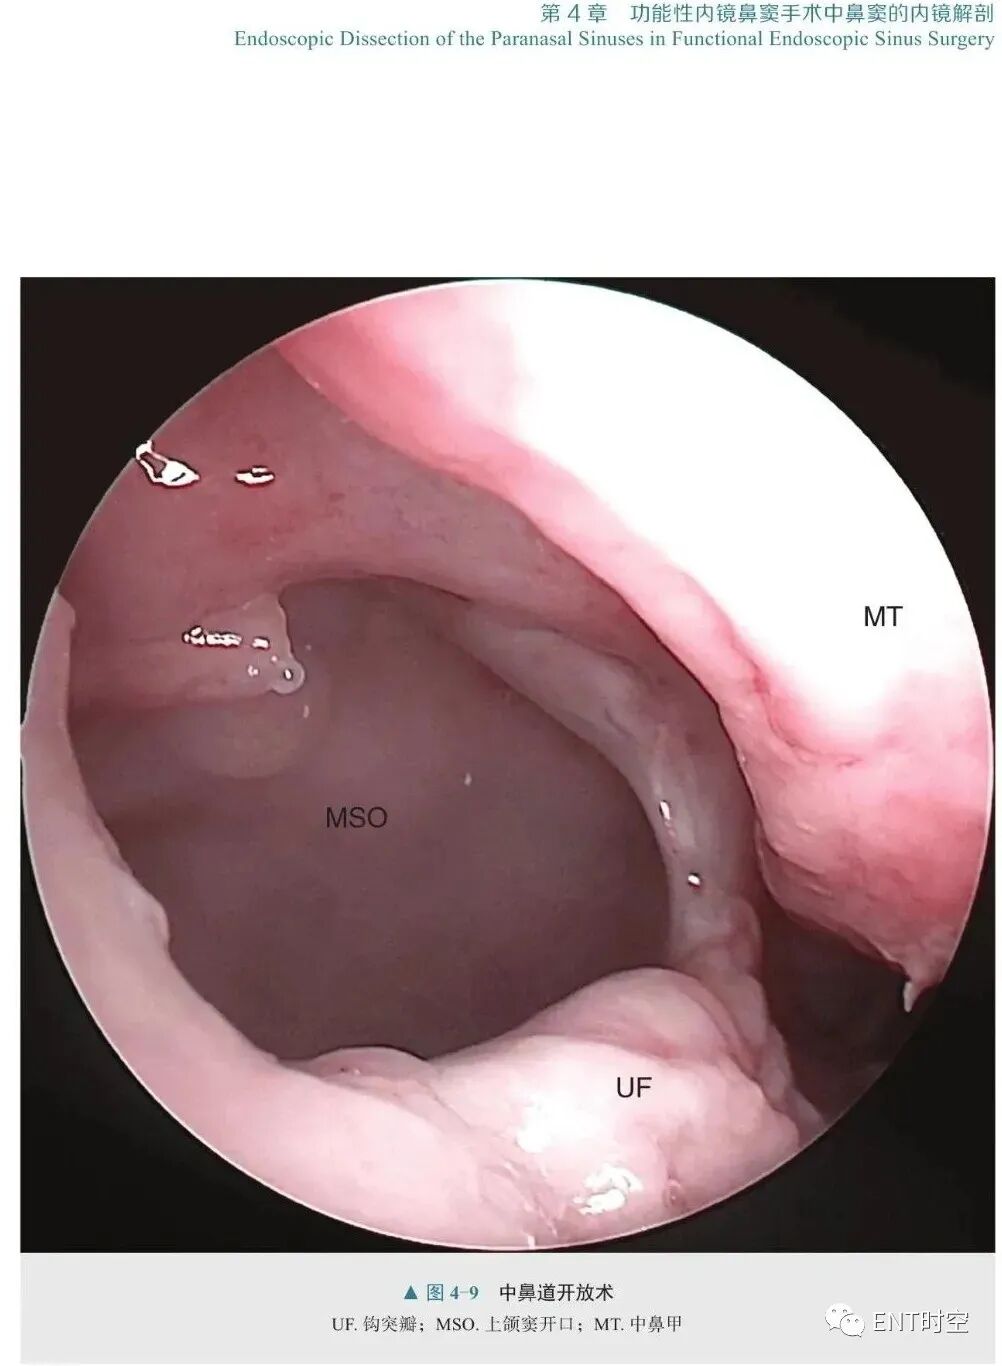

刘丕楠 主译《内镜解剖分步教程:鼻旁窦与腹侧颅底》是一部有关内镜下腹侧颅底解剖的实用操作教程。全书共8章,首先介绍了内镜的器械和基本操作过程,以及有关内镜手术的15条原则,之后开始介绍到达复杂颅底结构的各种入路,包括内镜入路到达鼻旁窦、腹侧颅底、脑神经及颅内间隙等。作者将内镜颅底外科整个手术通路的解剖结构做了层层递进式的描述,系统地展示了内镜下经鼻逐步暴露的各个重要环节,并通过精美生动的影像和图片全面展示了双人四手操作的精髓。本书内容新颖独特,图文并茂,适合有志从事神经内镜专科诊疗的医师、耳鼻咽喉科医师及神经外科医师阅读参考。

神经内镜是近20年发展起来的神经外科微创技术,是现代科学技术带给神经外科医生的一双“慧眼”,其以抵近观察和侧方视角的优势极大拓展了神经外科手术入路的选择。对于某些神经外科疾病,尤其是邻近或累及颅底腹侧面的病变,如颅咽管瘤、侵袭性垂体瘤、脊索瘤、脑脊液漏、翼腭窝肿瘤、颞下窝肿瘤等,神经内镜具有无可比拟的视野优势和解剖合理性。正因如此,近年来神经内镜手术在国内发展如火如荼,越来越多的神经外科医生希望掌握这项技术。鼻腔是内镜到达腹侧颅底的最主要手术通道,熟知、理解内镜视角下鼻腔、鼻旁窦及颅底腹侧解剖是开展内镜经鼻手术的必要前提。